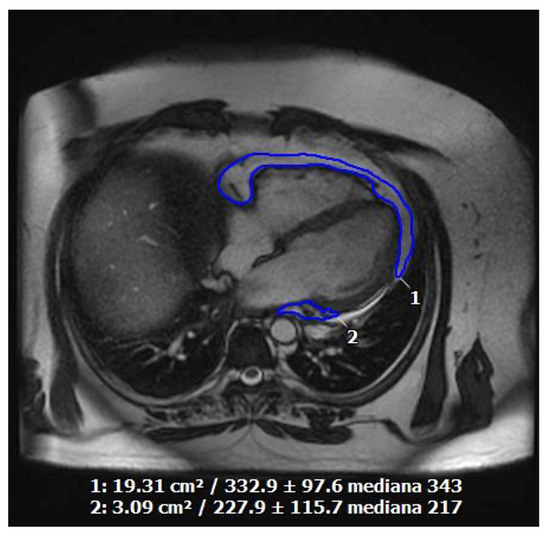

7. Coronary Artery Calcium Score

8. Coronary Computed Tomography Angiography

9. Standard and AI-Based Computer Tomography-Derived Flow Fractional Reserve